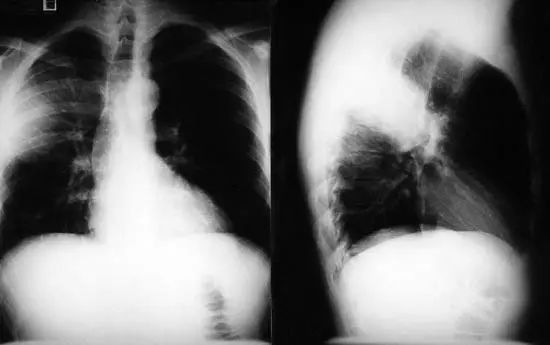

图1.1 细菌性肺炎。右上叶肺炎患者的放射影像。胸廓前后径增大,提示有慢性阻塞性肺疾病(COPD)。

图1.2 细菌性肺炎。双肺下叶肺炎患者影像。